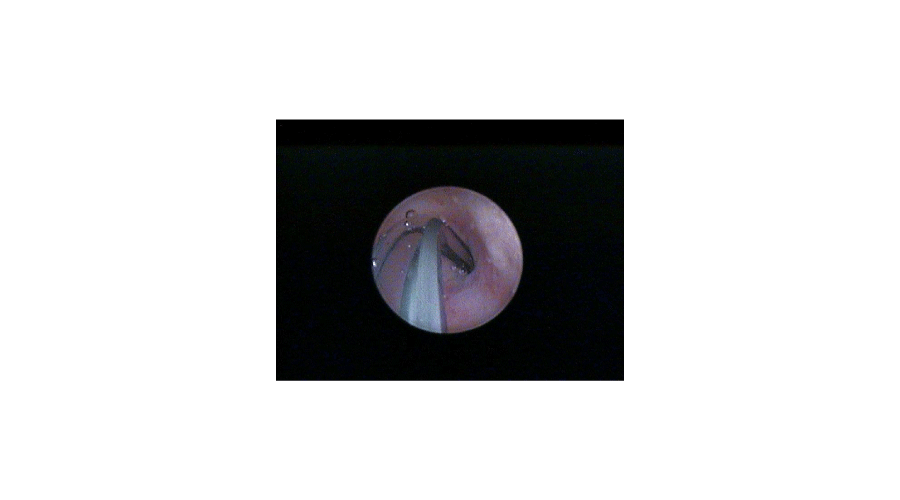

In the second step a 1.7 mm plastic catheter (Cavafix, B-Braun) is inserted through the working channel of the sheath and the tip is placed to the tubal ostium (Figures 1,2). During selective pertubation, each Fallopian tube is considered as a diagnostic unit. By rotating the hysteroscope, the direction of the catheter can be modified toward the ostium. The cone shape of the tubal ostium will help in leading the tip of the flexible catheter into the ostium. The catheter should not to be inserted into the tube, only the tip should be placed at the entry of it. Through the catheter 2-10 ml of methylene blue dye (Patente Blue, 2 ml in 1000 ml saline) is injected slowly. In case of a patent Fallopian tube no blue fluid will appear in the uterine cavity. Normal color of the endometrium can be seen, while the transparent catheter turns blue, due to the methylene blue flowing inside it (Figure 3). Occluded Fallopian tube changes the uterine cavity into blue, due to the back-flow of the methylene blue (Figure 4). In case of corneal occlusion, blue dye will flow back immediately. If the blockage is at the distal part of the tube, the first fraction of the blue dye will disappear and after some time of the injection will the back-flow be detectable. After the evaluation of tubal patency, blue dye clears up within 5-10 seconds and the whole procedure can be repeated on the other side. To be more exact and precise, transvaginal ultrasound examination should be performed before and after the hysteroscopy. This examination can exclude any pathology of the tubes that can cause false negative results, for example hydrosalpinx. By detecting free fluid around the ovaries and in the pouch of Doulas, the result of the perturbation can be verified. Total examination time is 4-8 minutes. As usual after office hysteroscopy, there is no need for post-operative observation, and the procedure can be performed with a high patient compliance [5].